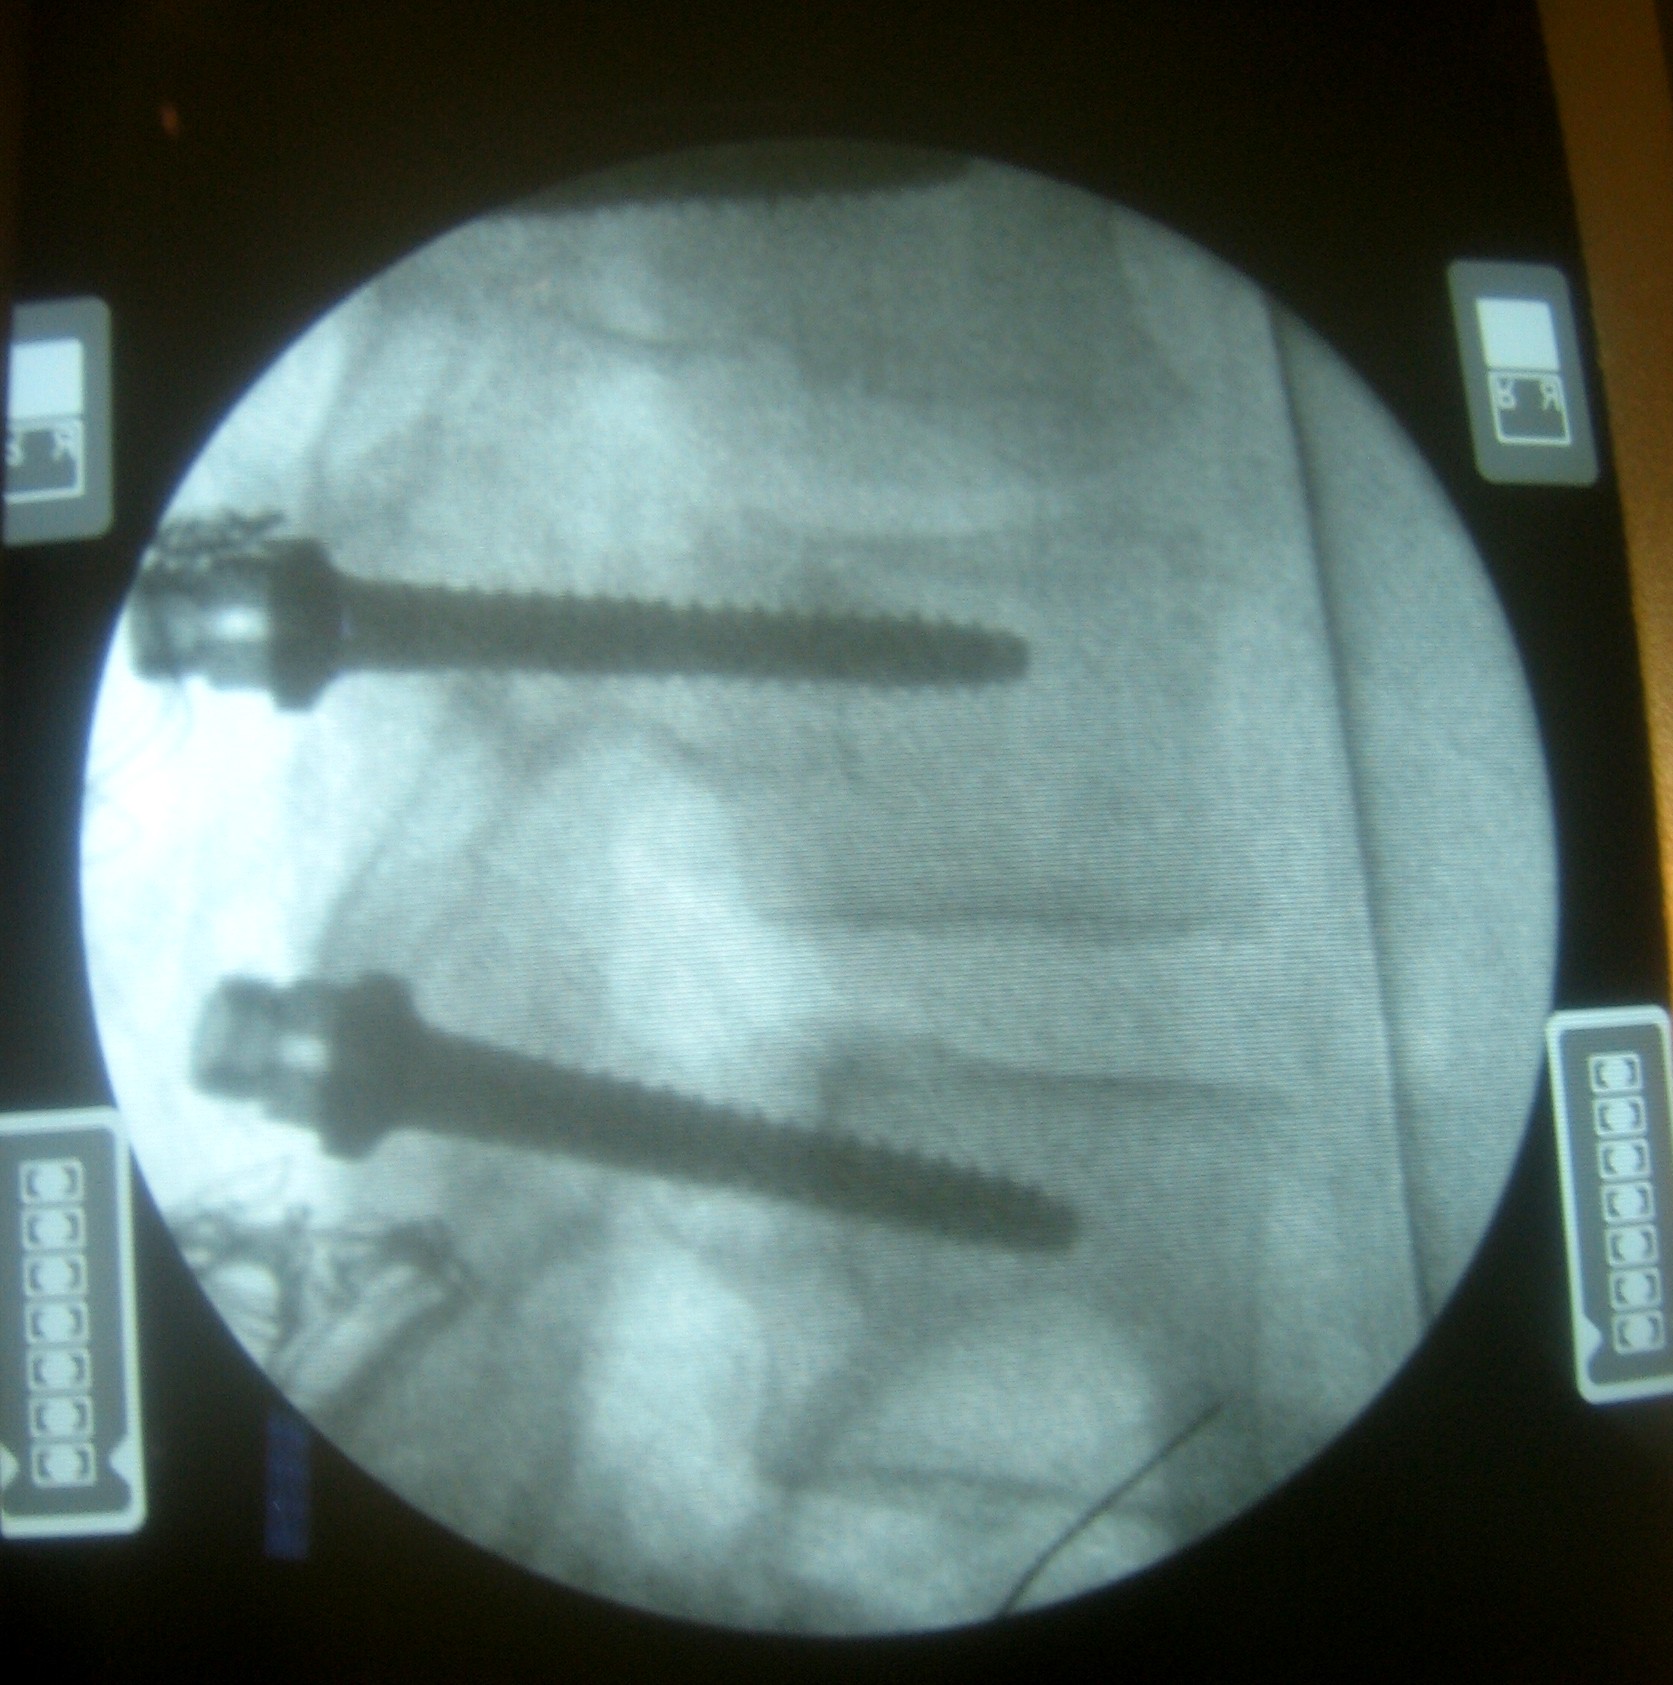

Foto de: escoliosis

En primer lugar se introduce en la vertebra una especie de punzon con el que se encuentra el punto de entrada de los tonillos y se abre el camino que facilitara la introducción de estos posteriormente.

escoliosis